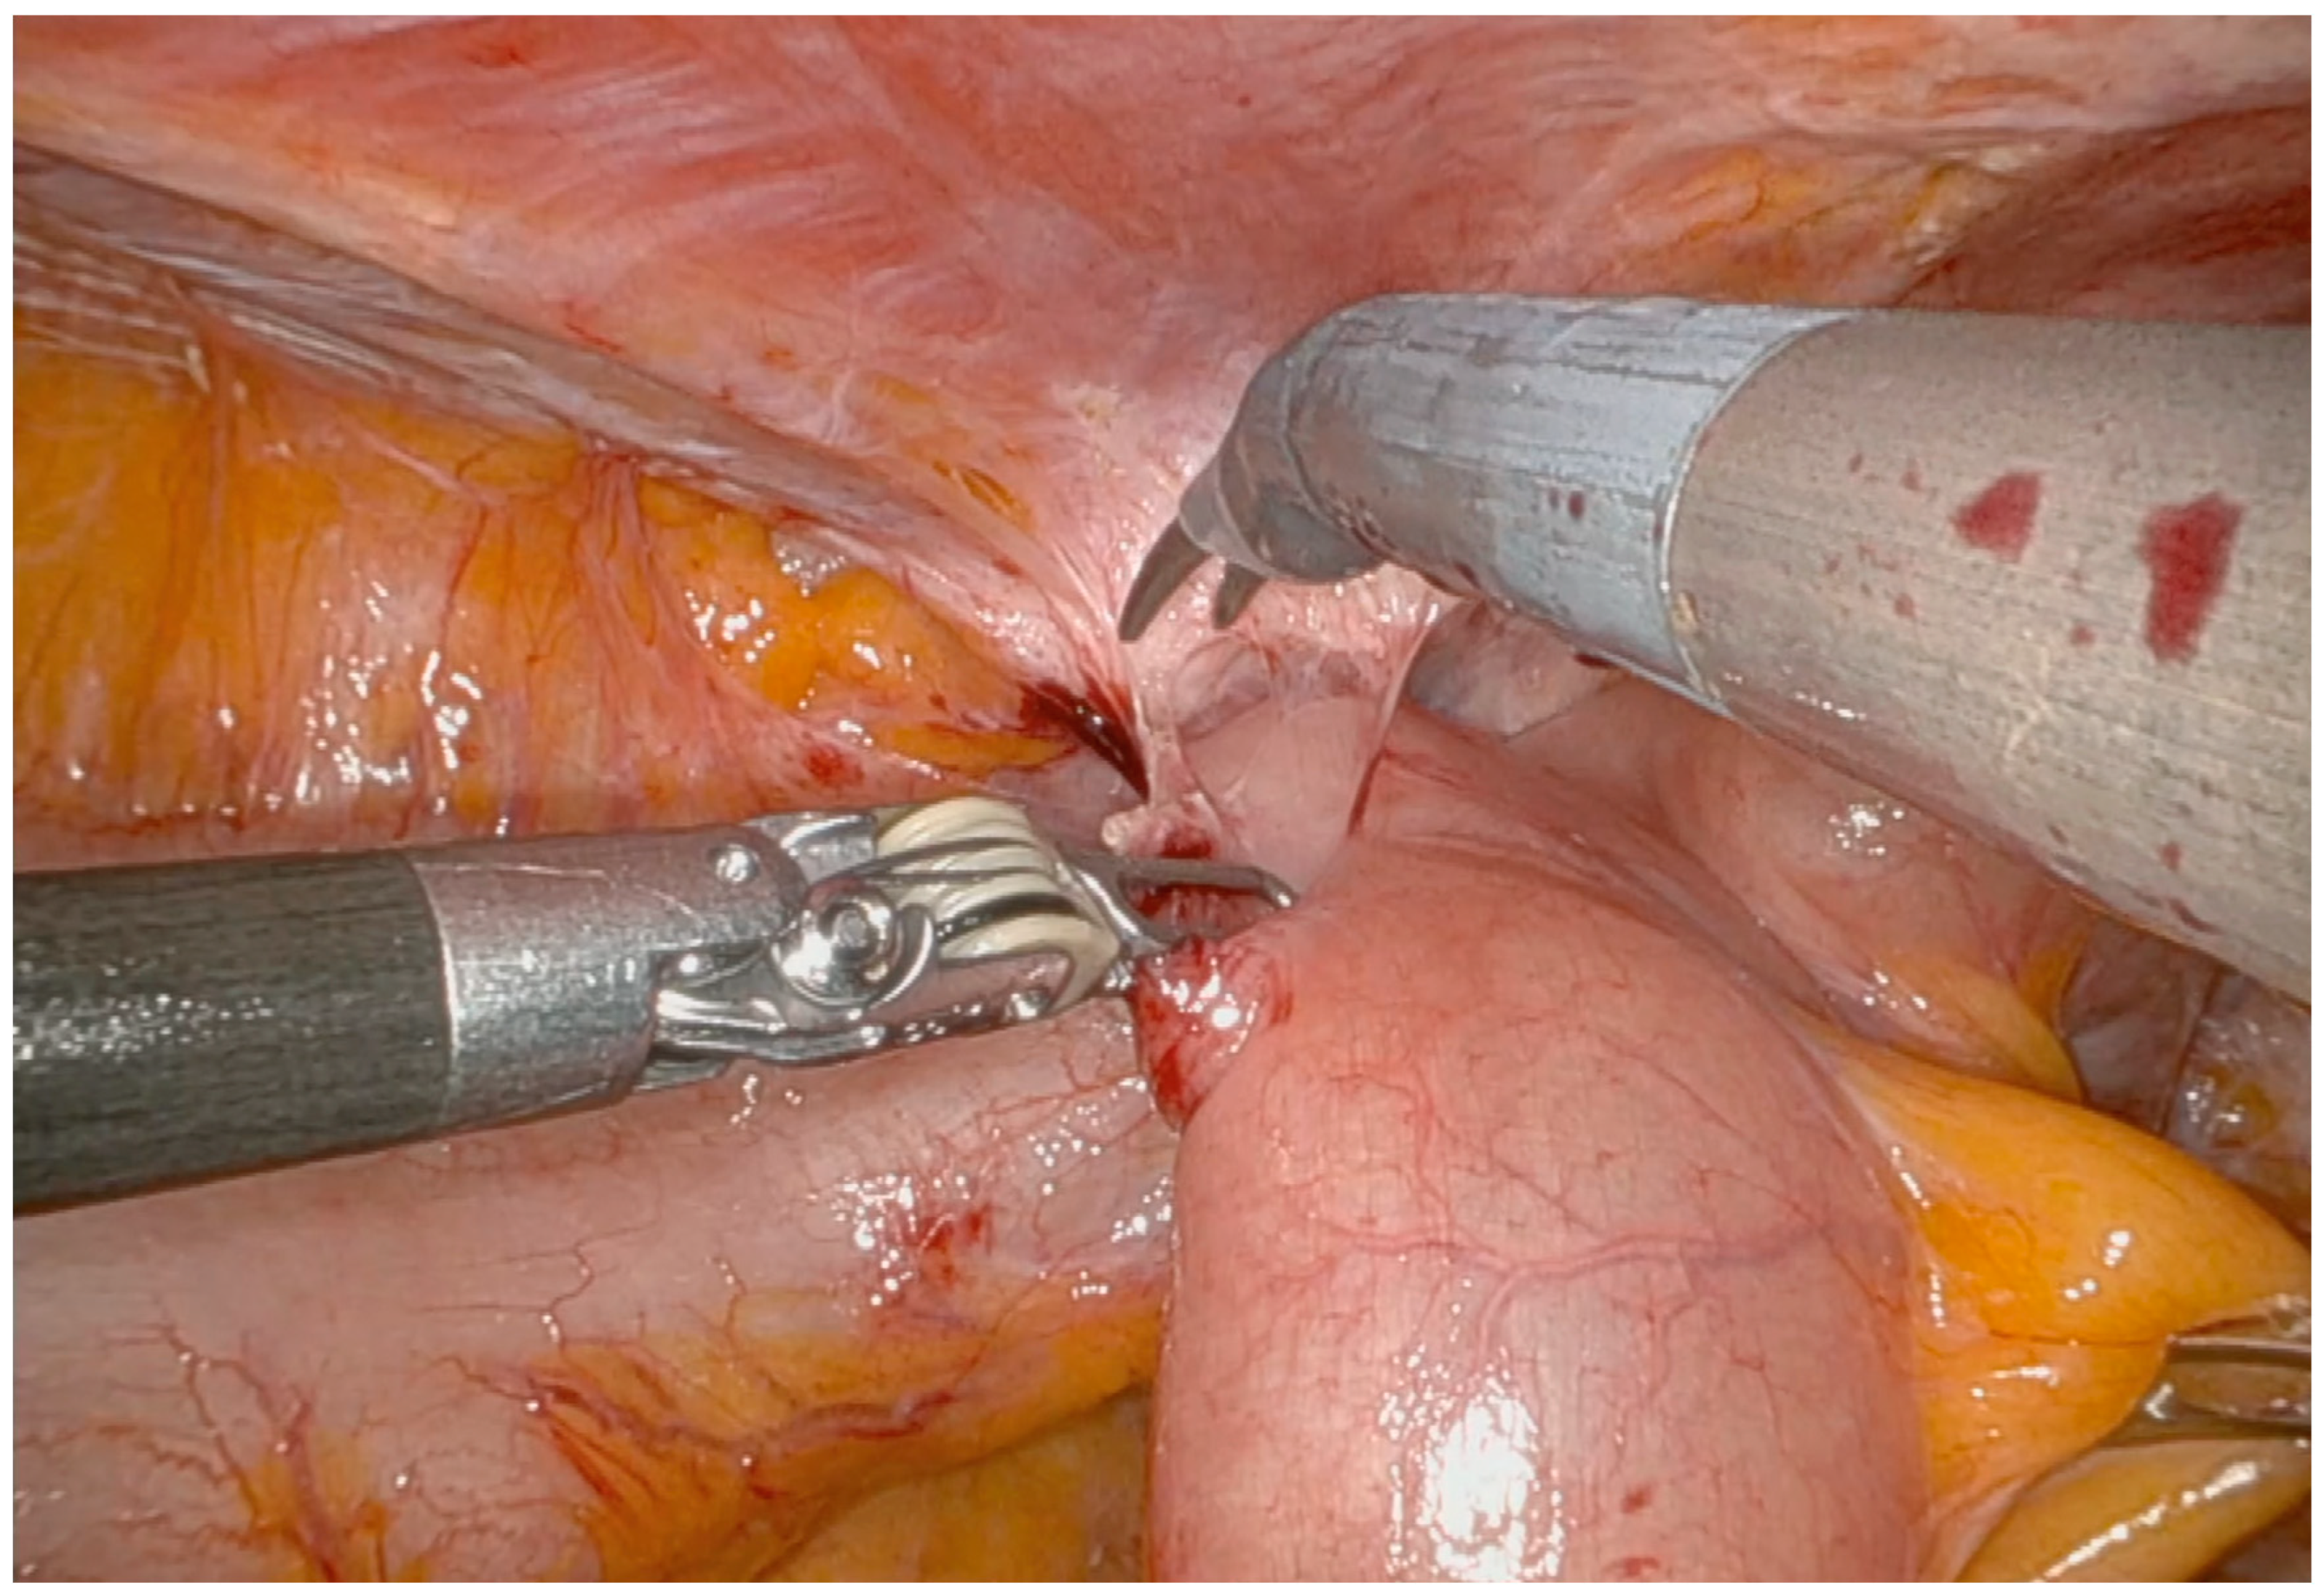

Operative Technique